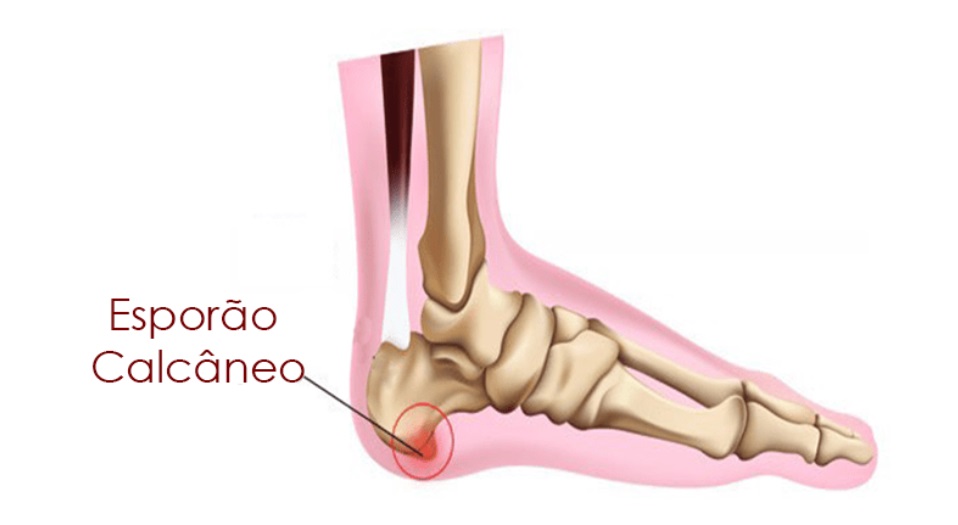

É o resultado do crescimento anormal de um pequeno segmento do osso do calcanhar, que se forma na parte de baixo ou na região posterior desse osso. As mulheres são as que mais sofrem com o problema, segundo explica o médico ortopedista Ludovico PierI Neto.

O Esporão é uma calcificação “espícula” óssea que se forma na parte inferior ou posterior do ósseo calcâneo. Ele se forma em resposta ao impacto excessivo, esforço ou peso acima do esperado. O esporão pode ou não estar associado a dor. Algumas vezes não gera dor que acontece quando o esporão pressiona a fáscia plantar, conhecida como fasceite. “A fascite plantar é uma inflamação que acomete a fáscia plantar, membrana que se estende desde o osso calcâneo até os dedos do pé. Já o esporão do calcâneo é uma saliência óssea que se projeta na base ou atrás do osso calcâneo”,

Existem alguns tipos de esporão. O plantar é o mais comum, o esporão posterior junto ao tendão calcâneo também chamado de Aquiles , e que leva a uma inflamação local chamada “doença de Haglund” (A síndrome de Haglund é uma deformidade do osso e dos tecidos no calcanhar que pode causar inflamação, dor e inchaço).